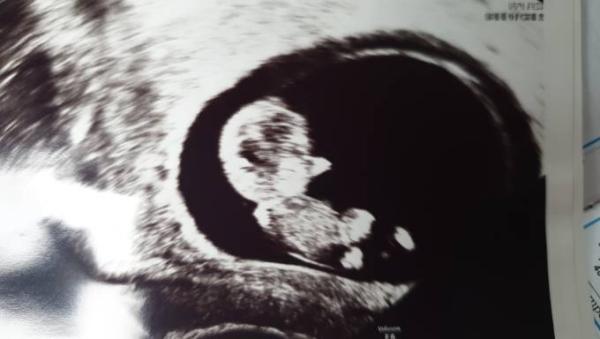

Hallo ihr, Gestern gab es das erste Screening. Das Baby ist gut entwickelt, hat gestrampelt und sich bewegt und ich musste weinen, als ich das gesehen habe. Ich bin so glücklich mit meinem Würmchen. Und ab heute sind wir im 4ten Monat. Bauch sieht man leider noch nicht, dafür habe ich etwas zu viel Speck, aber ich hoffe, dass der Bauch bald zu sehen ist.

Bild zu Hallo zweites Trimester - Forum für Januar - Mamis